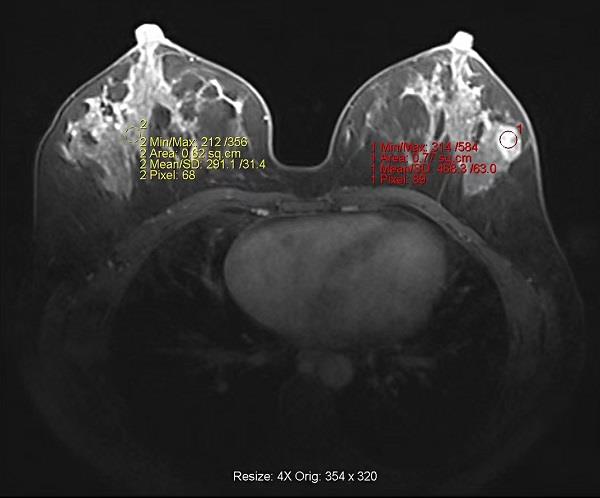

乳腺磁共振成像是一種無(wú)創(chuàng)的行之有效的檢查方法,可從不同方位、多序列對(duì)乳腺進(jìn)行重復(fù)成像。目前乳腺磁共振檢查已被廣泛應(yīng)用,其適用范圍包括:分析常規(guī)檢查不能確定的乳腺病變、致密性乳腺局部腫瘤的分期、手術(shù)治療殘余乳腺或懷疑復(fù)發(fā)的腫瘤、隱匿性乳腺癌與已知的轉(zhuǎn)移、評(píng)估治療的效果等。磁共振以其特有的彌散加權(quán)功能成像(DWI),配合常規(guī)T1、T2序列,能發(fā)現(xiàn)乳腺內(nèi)微小的病灶,對(duì)于某些特異性不高的病變,進(jìn)行動(dòng)態(tài)對(duì)比增強(qiáng)磁共振成像,直觀顯示病灶血供特征,對(duì)動(dòng)態(tài)增強(qiáng)曲線(TIC)分析,結(jié)合BI-RADS MRI評(píng)分標(biāo)準(zhǔn),進(jìn)一步提高病變的檢出率和良惡性質(zhì)的判斷,避免不必要的活組織檢查,使乳腺磁共振的臨床應(yīng)用價(jià)值得到了進(jìn)一步提高。